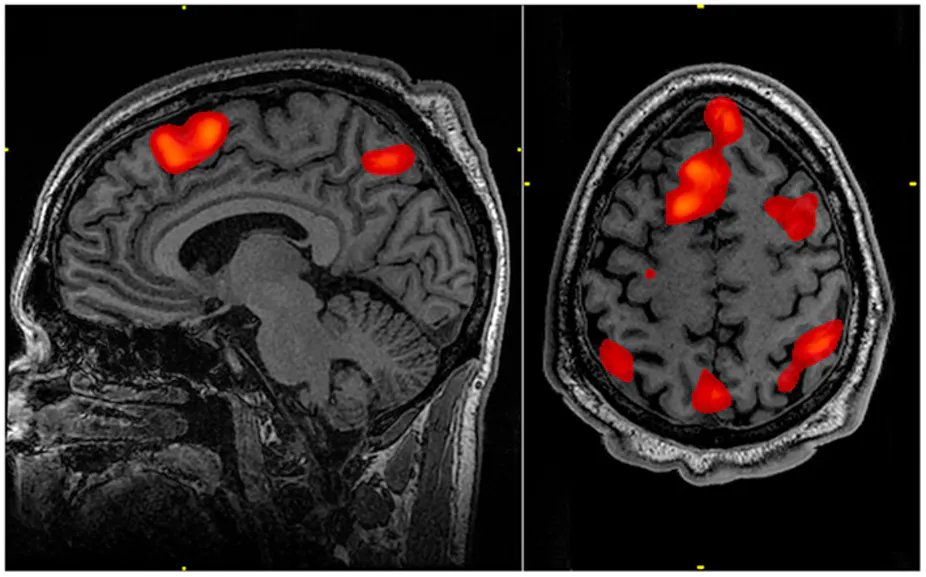

fMRI

functional MRI

localized brain activity